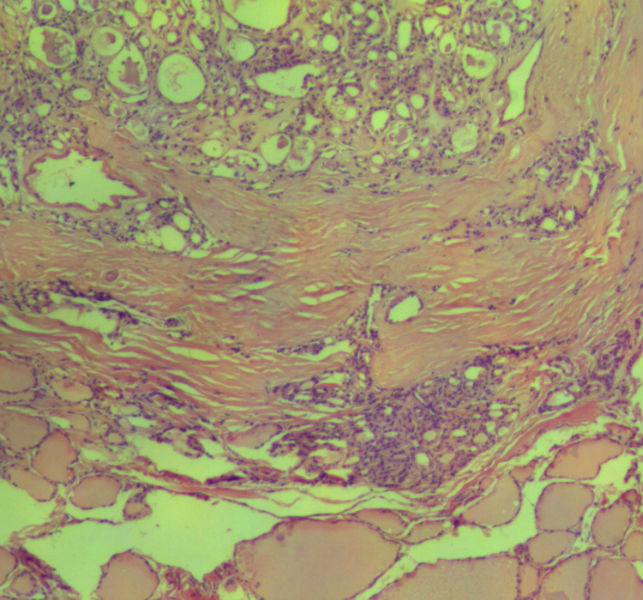

女,45岁,体检发现颈前区一结节,术中送检甲状腺左腺叶,发现一界清结小1*0.8cm,灰黄色。术中诊断滤泡性肿瘤伴包膜累及,局部疑包膜穿破,滤泡癌可能,待石蜡报告。石蜡连续切片形态见图,可见明显包膜穿破,诊断为滤泡性癌。患者借片到上级医院会诊,结果为:包膜内滤泡癌伴包膜累及。请问有包膜内滤泡癌的提法吗?这个病例怎么诊断啊?请各位老师多指导。

• 这个是滤泡性癌吗图2

图2